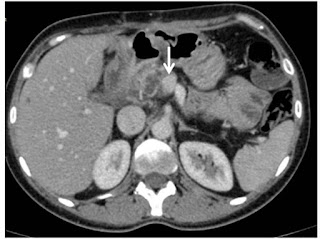

Determined to fight her disease, in October 2018, Ms A attended Outpatients’ Clinic of the Department of Surgical Gastroenterology at Max Hospital, Saket, New Delhi. She underwent a through re-evaluation by a multidisciplinary team. Her PET – CT scan revealed that the tumor was confined to the pancreas with no spread to other organs of the body. The pancreatic protocol CT scan showed the tumor involved major adjacent blood vessels (Figure 1).

Figure1. Pre CRT Pancreatic protocol CT scan

Tumor infiltrating SMV (> 180 degrees) with contour abnormality